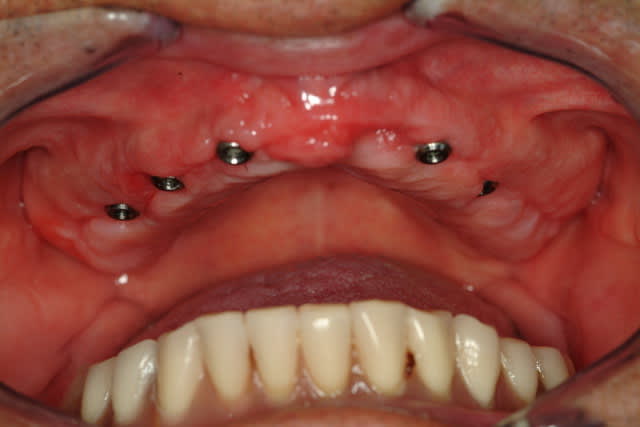

J'ai abandonné la MCI au maxillaire sur 4 implants c'est trop risqué.

Aucun filet de secours, je préfère avoir au moins 6 implants bloqués à min 30 Ncm, pour mettre en charge un maxillaire complet.

A la mandibule 4 implants, ça fonctionne très bien, j'en ai fait beaucoup aussi.

Voici déjà un cas avec 6 implants maxillaire et mandibulaire.

Le maxillaire a été fait en 2009 et la mandibule en 2007.